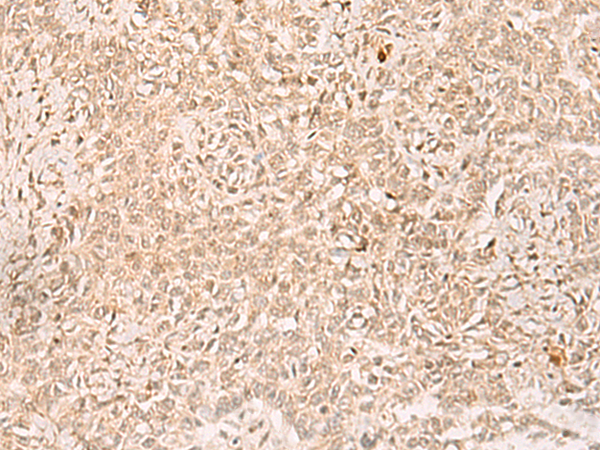

分类: 科研抗体货号: P02992别名: RBTN3; RHOM3; RBTNL2; Rhom-3应用: WB,IHC反应种属: Human, Mouse, Rat